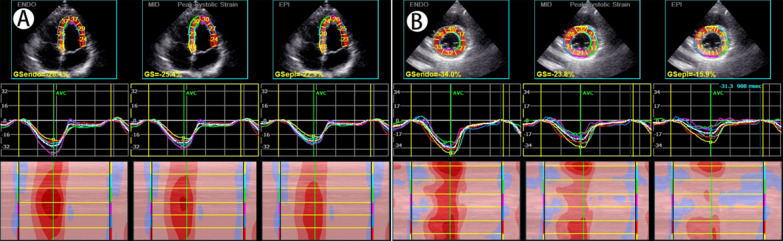

Methods: Forty-eight newly diagnosed, untreated patients with POI (POI group) and fifty healthy female subjects matched for age, height and weight (control group) were enrolled. Standard transthoracic echocardiography was used to measure conventional parameters and layer-specific strain parameters.The layer-specific strain parameters included subendomyocardial global longitudinal strain (GLSendo), mid-layer myocardial global longitudinal strain (GLSmid), subepimyocardial global longitudinal strain (GLSepi), subendomyocardial global circumferential strain (GCSendo), mid-layer myocardial global circumferential strain (GCSmid), and subepimyocardial global circumferential strain (GCSepi).

Results: There were no significant differences in age, body mass index (BMI), blood pressure, or left ventricular ejection fraction (LVEF) between the two groups. The end-diastolic interventricular septal thickness (IVST) was greater in the POI group (8.29 ± 1.32 vs. 7.66 ± 0.82, P = 0.008), and the POI group had lower E, E/A, and lateral e' (all P < 0.05). As for systolic functions,the POI group had lower GLSendo, GLSmid, GLSepi, GCSendo, GCSmid, and GCSepi (all P < 0.05).The intraobserver and interobserver coefficients of GLSendo, GLSmid, GLSepi, GCSendo, GCSmid, and GCSepi were greater than 0.900.

Conclusions: POI patients with normal LVEF may suffer from subclinical left ventricular myocardial systolic dysfunction. Echocardiography of layer-specific myocardial strain could more sensitively detect subclinical impairment of left ventricular systolic function in POI patients.